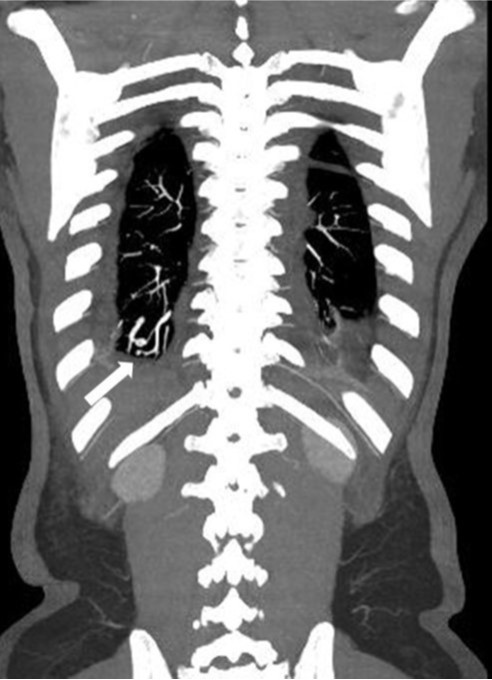

조영증강 흉부 CT에서 우폐하엽 후저구역(posterior basal segment)에 폐동맥과 유사한 정도의 조영증강을 보이는 직경 8mm 크기의 종괴가 관찰된다. 이 종괴는 우하엽 폐동맥 및 폐정맥과 연결성이 관찰되고 있다.

Fig. 1.

Fig. 1. Coronal contrast-enhanced chest CT image shows a small pulmonary arteriovenous malformation (arrow) in the posterior basal segment of the right lung.